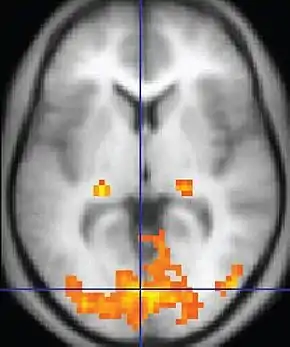

![]() An fMRI image with yellow areas showing increased activity compared with a control condition | |